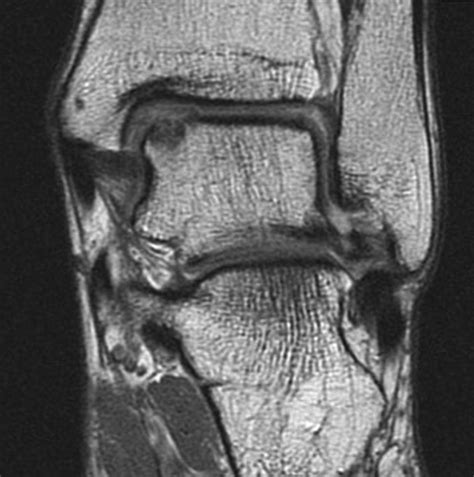

Osteochondral Lesions - Clinical Tree